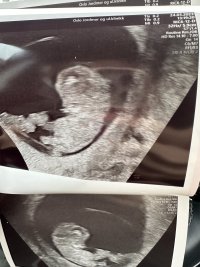

Ble målt til 12+6.

7+4 vs 9+1. Selv om de 11 dagene kjentes ut som 2 mnd! 9+1 og spretter litt rundt inni der

Klarte ikke å vente en hel uke til, men ble så letta og glad

Hilsen hu som er 9+1 og som har vært på sin tredje UL i dag